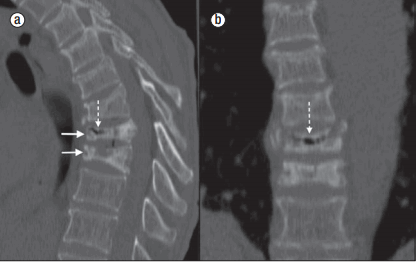

(Слева) Сагиттальный срез, Т2-ВИ: полосовидное скопление газа в теле позвонка и в межпозвонковых дисках. Подобные МР-изменения отличаются меньшей выраженностью и меньшей специфичностью по сравнению с КТ-картиной.

(Справа) На этом сагиттальном КТ-срезе определяются скопления газа в коллабированном теле позвонка. В данном случае эти изменения обнаружены у пациента с метастатическим поражением, для которых подобная картина нетипична. Признаки болезни Кюммеля не всегда свидетельствуют о доброкачественном характере компрессионного перелома. У данного пациента, в частности, имело место бластическое метастатическое поражение на фоне рака предстательной железы.